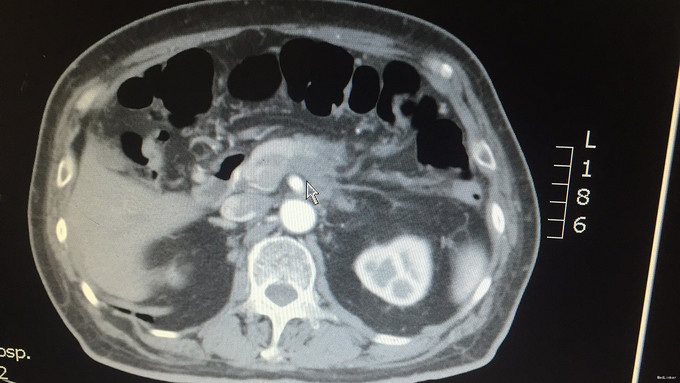

查体:腹部平坦,未见腹壁紧张及腹壁静脉曲张,无肠型及蠕动波;腹平软,无压痛、反跳痛、肌紧张等,未及明显异常,肝区无叩击痛,移动性浊音(—),肠鸣音4次/分,无增强或减弱。振水音(+)。 辅查:外院血癌胚抗原:41.39ng/ml;外院上腹部MRI增强:胰腺体尾部占位,考虑恶性,胰腺癌可能性大。我院上腹部CT平扫+增强:胰腺体部以远前后径约2.6cm,平扫CT值约50HU,增强后动脉期及门脉期CT值约68HU。胰胃间隙及胰后间隙稍模糊,可见数个淋巴结影,最大者长径约9.2cm。左侧肾上腺后支稍饱满,似可见一长径约1cm稍高密度影。[印象]:1.胰腺体尾部占位,恶性可能;2.腹腔内及腹膜后数个淋巴结;3.左侧肾上腺饱满,清结合临床。我院肿瘤指标检查:CA19-9:4.13U/ml,CEA:34.91U/ml,AFP:5.40U/ml。